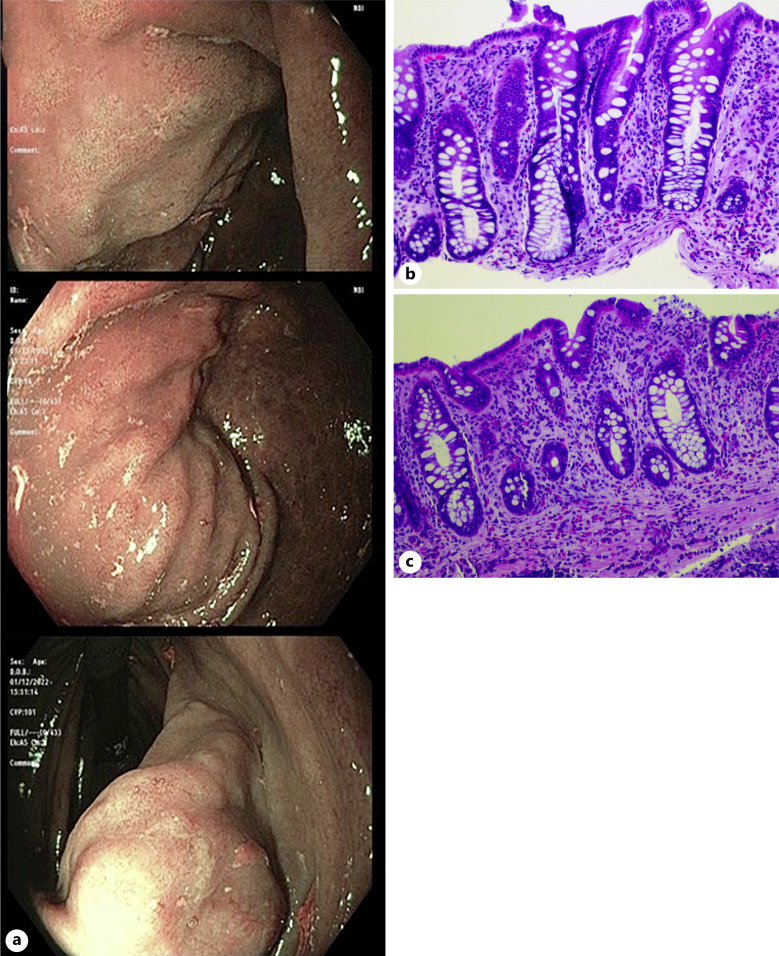

导读:蛔虫科包括至少50种肠道线虫,其中粪形蛔虫是人类中最常见的一种。由于这种寄生虫复杂的生命周期,它既可以局限于肠道,也可以传播到全身的不同器官,在免疫抑制的情况下最终导致过度感染。类圆线虫病在美国是罕见的,并伴有胃累及是罕见的。病例介绍:在这个病例报告中,我们描述了一个无症状和免疫能力的利比里亚胃十二指肠圆线虫病患者的病例,其诊断是基于内镜评估缺铁性贫血的组织学结果。结论:本病例提示在缺铁性贫血合并外周血嗜酸性粒细胞增多的高危人群中怀疑弥散性圆线虫病诊断的重要性。

Introduction: The Strongyloidae family includes at least fifty species of intestinal nematode worms, and Strongyloides stercoralis is the most prevalent one among humans. As a result of this parasite's complex lifecycle, it can either remain localized in the intestines or disseminate to different organs throughout the body, culminating in hyperinfection in case of immunosuppression. Strongyloidiasis is rarely encountered in the USA, and an associated gastric involvement is uncommon.

Case presentation: In this case report, we describe the case of an asymptomatic and immunocompetent Liberian patient with gastroduodenal strongyloidiasis whose diagnosis was based on histologic findings during endoscopic evaluation for iron deficiency anemia.